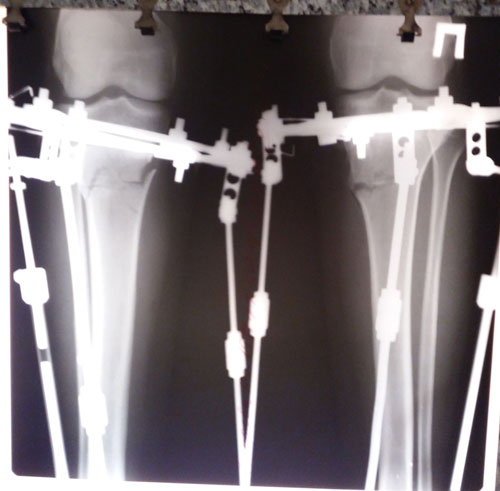

Дата операции 17.10.2017г.

Дата снятия аппаратов 25.01.2018г.

Срок лечения 98 дней.